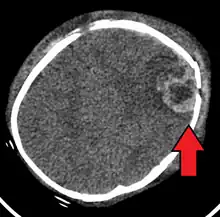

Shaken baby syndrom

Shaken baby syndrom forekommer, hvis et spædbarn er blevet voldsomt rystet, og det derved har fået revet mange, små blodårer over. Der er stor risiko for, at barnet kan dø, og i cirka 70 % af tilfældene medfører ruskevold følgesygdommme som epilepsi, blindhed eller varige hjerneskader.[1]

CT-scanning af spædbarn med rysteskader i hjernen